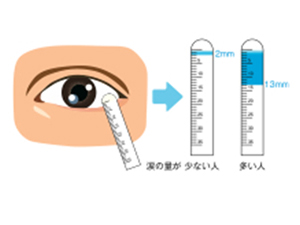

飛蚊症

視界にごみや虫のようなものが飛んでいるように見える症状を飛蚊症と呼びます。特に治療が必要でない「生理的」なものと、治療をしないと視力が低下する恐れのある「病的」なものに分けられます。

| 考えられる原因 |

生理的飛蚊症 硝子体(しょうしたい)が年齢により濁るためにおこります。 病的飛蚊症 網膜剥離、網膜裂孔、硝子体出血、ぶどう膜炎などの疾患により付随して起こる飛蚊症です。手術や処置などの早期治療を行わないと失明する恐れもあります。 |

| 検査 |

|

| 主な治療法 |

生理的な飛蚊症の場合は、特に治療はありません。 |

網膜剥離・網膜裂孔

網膜剥離とは、眼球の内側にある網膜という膜が剥がれて、はがれた部分の視野が欠けたり、網膜の中心部である黄斑部分まで剥がれた場合は、急激に視力が低下し、失明に至る恐れもあります。